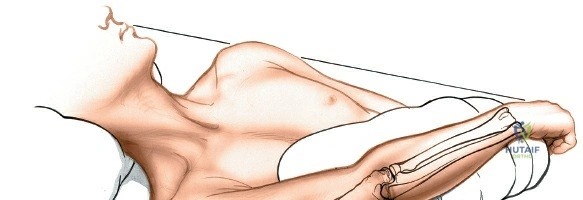

Patient Positioning and Operating Room Setup

Place the patient supine on the operating table. The affected upper extremity is extended onto a radiolucent hand table or arm board. The shoulder should be abducted to approximately 90 degrees, and the elbow extended. A pneumatic tourniquet is applied high on the brachium. The setup must allow for unimpeded use of intraoperative fluoroscopy (C-arm), which should be positioned parallel to the arm board to allow for easy anterior-posterior and lateral imaging without compromising the sterile field.

Accurate identification of surface landmarks is the first step in a successful Henry approach. Palpate the biceps tendon, a stout, taut structure crossing the anterior elbow joint just medial to the brachioradialis muscle. Next, palpate the brachioradialis itself, the fleshy muscle forming the lateral border of the cubital fossa. Finally, identify the styloid process of the radius distally. Note that when the forearm is fully supinated (the anatomic position), the radial styloid is truly lateral.

Make a straight or gently curved incision beginning at the anterior flexor crease of the elbow, just lateral to the biceps tendon. Extend this incision distally toward the styloid process of the radius. The exact length and placement of the incision are dictated by the specific pathology; the approach is highly modular, and often only the proximal, middle, or distal third of the incision is required.